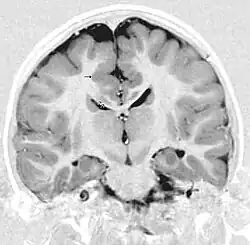

Gray matter heterotopia

Gray matter heterotopia is a neurological disorder caused by gray matter being located in an atypical location in the brain.[1]

Periventricular means beside the ventricle, while subependymal (also spelled subepydymal) means beneath the ependyma; because the ependyma is the thin epithelial sheet lining the ventricles of the brain, these two terms are used to define heterotopia occurring directly next to a ventricle. This is by far the most common location for heterotopia. Patients with isolated subependymal heterotopia usually present with a seizure disorder in the second decade of life.

Subependymal heterotopia present in a wide array of variations. They can be a small single node or a large number of nodes, can exist on either or both sides of the brain at any point along the higher ventricle margins, can be small or large, single or multiple, and can form a small node or a large wavy or curved mass.

Detection of heterotopia generally occurs when a patient receives brain imaging—usually an MRI or CT scan—to diagnose seizures that are resistant to medication. Correct diagnosis requires a high degree of radiological skill, due to the heterotopia's resemblance to other masses in the brain.